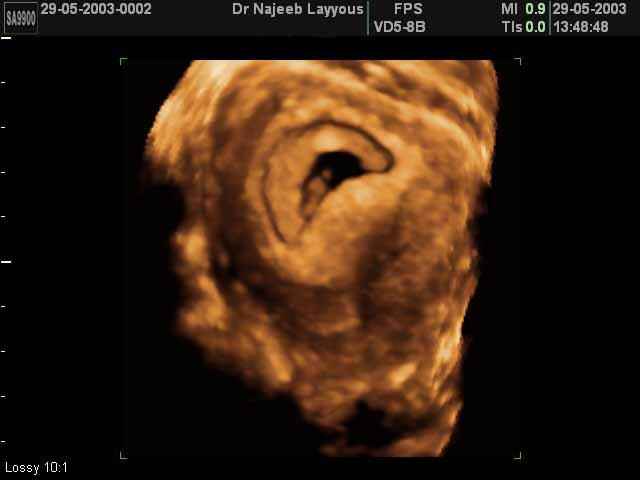

- 3D Photos Ecographie du Premier Trimestre